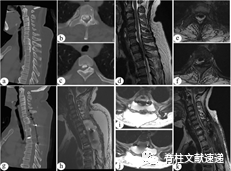

图注:一名PMC患者接受了翻修手术。a-f术前CT和MRI显示T1-10 OLF。g 在C6–T5进行椎板切除减压。h–j 初次手术后6个月发现切口肿胀和下肢肌无力。MRI显示巨大PMC的形成和脊髓受压。病人接受了翻修手术。k翻修术后3个月的MRI显示PMC完全吸收。